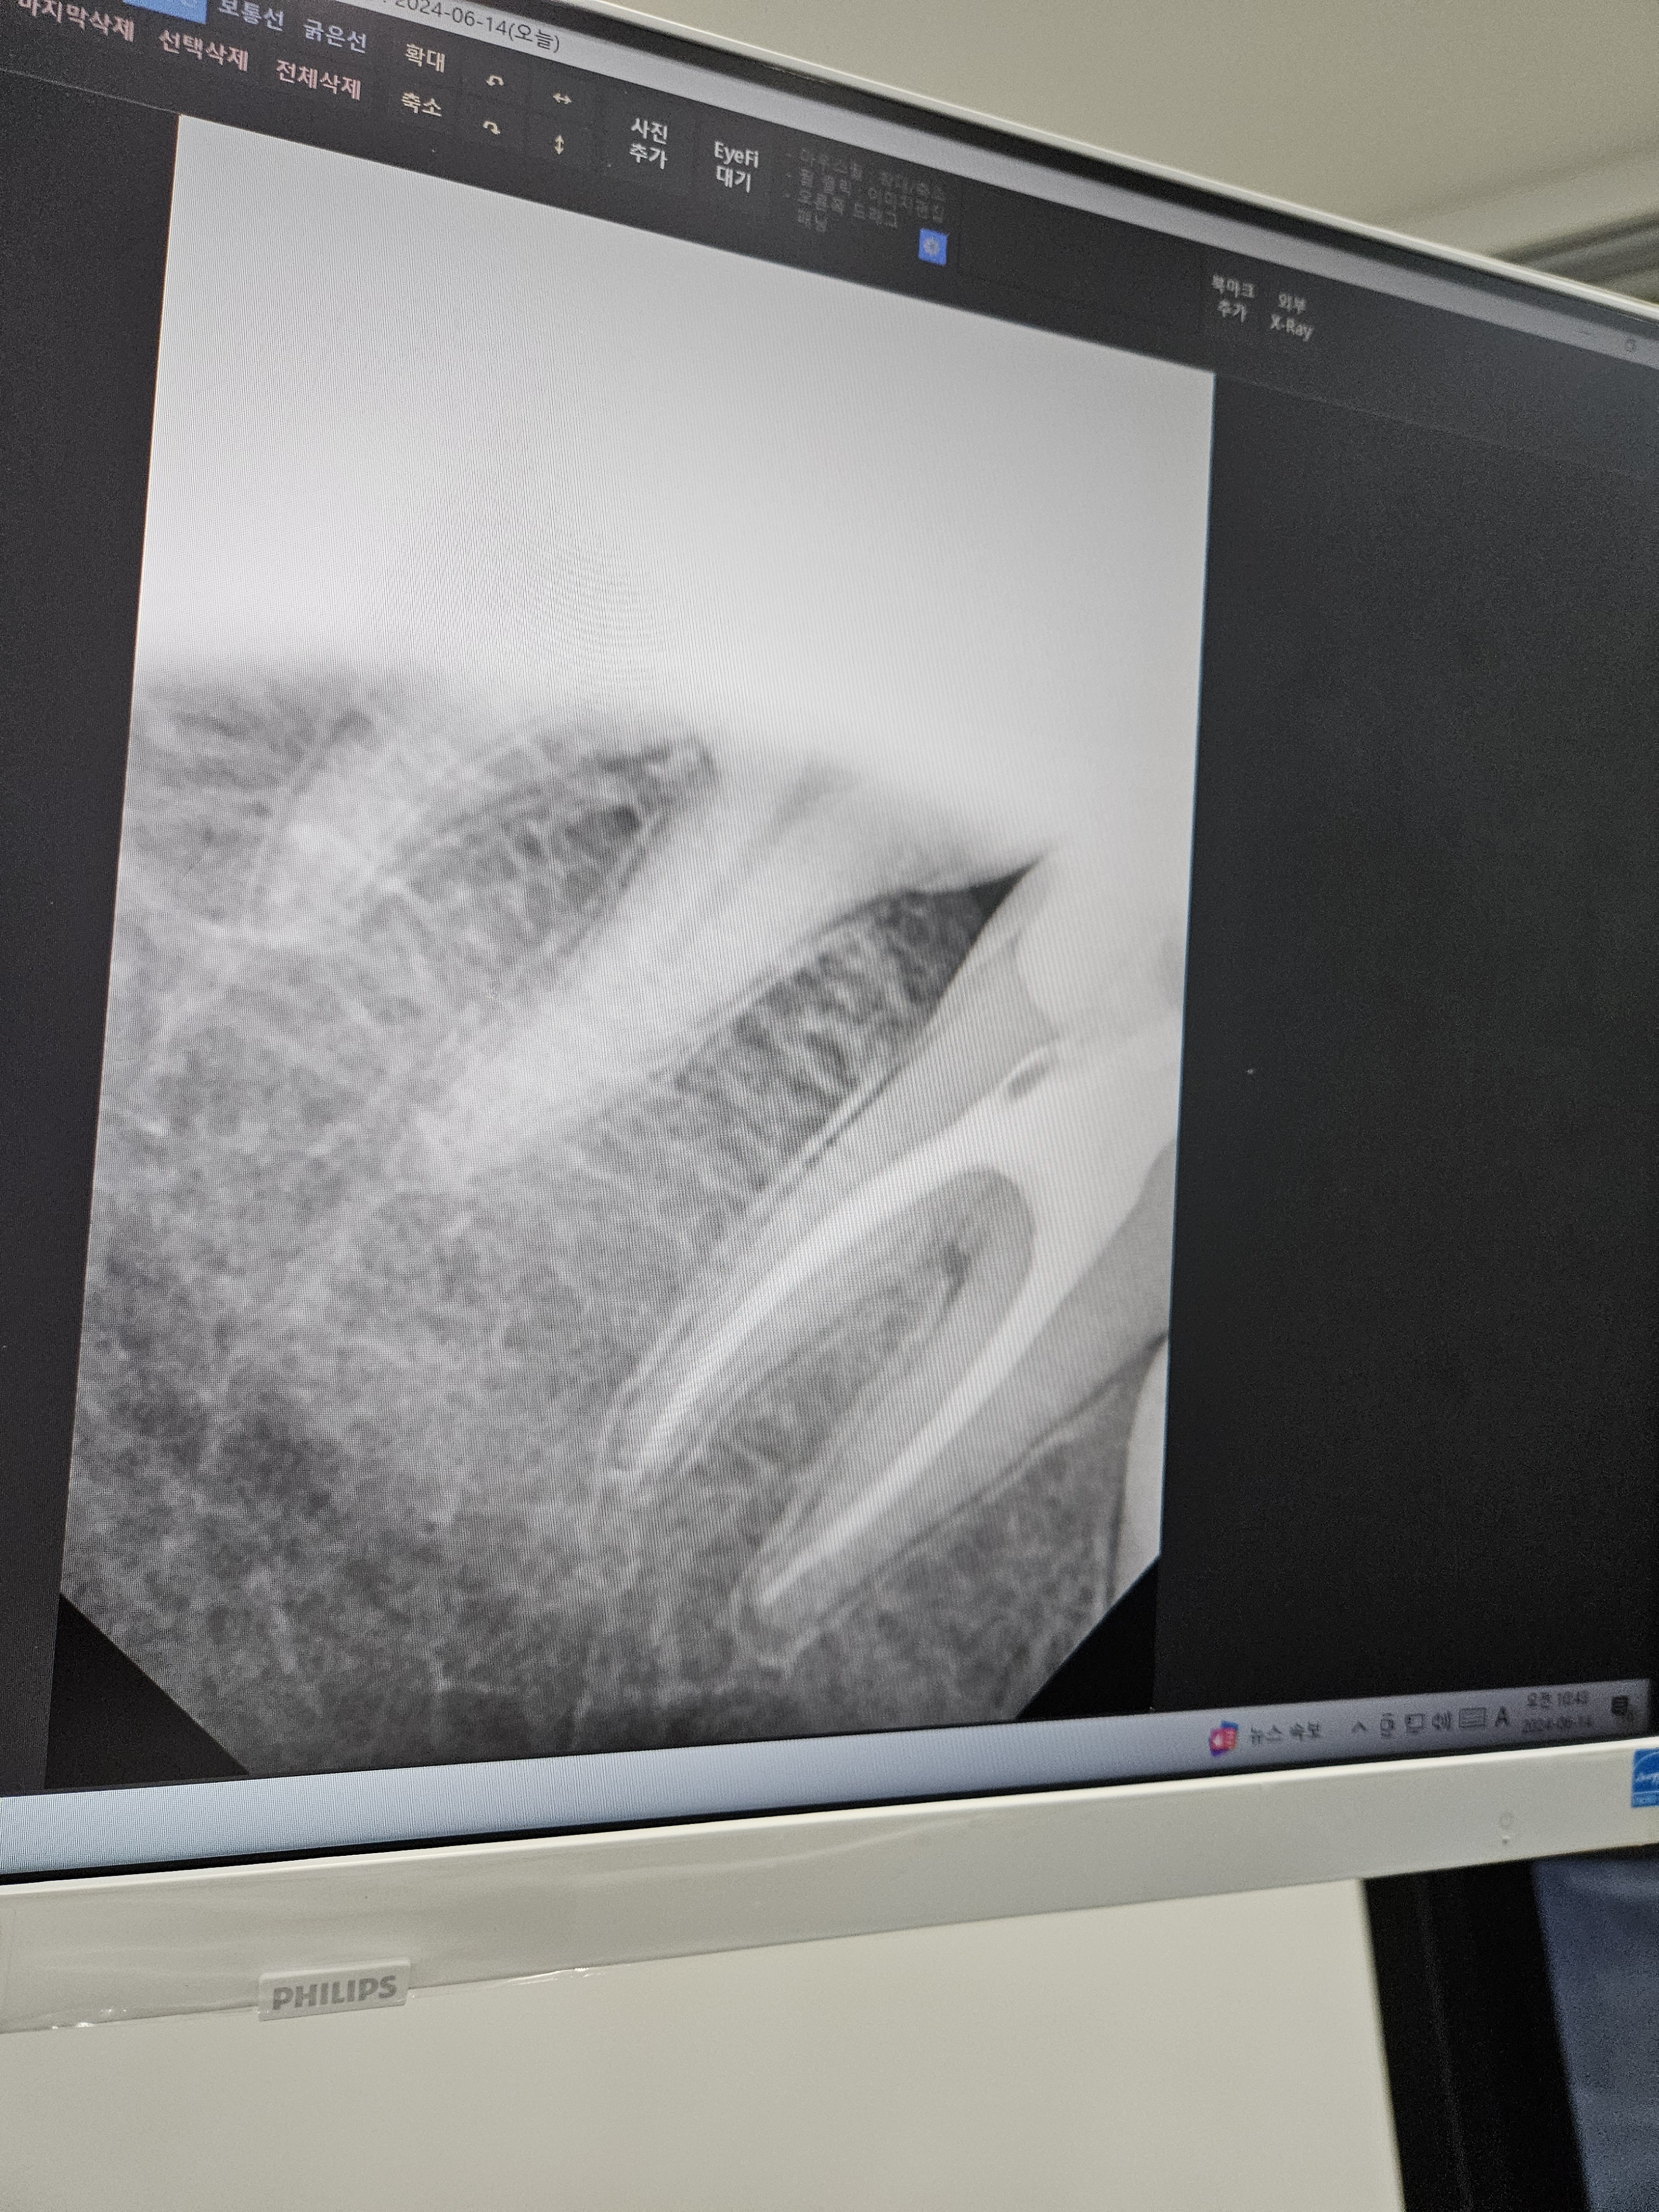

사진은 신경치료 후 안을 채운 후 사진 .. ㅜㅜ

잘 채워졌다고 이야기는 하는데 왜 이렇게 아플까요..?